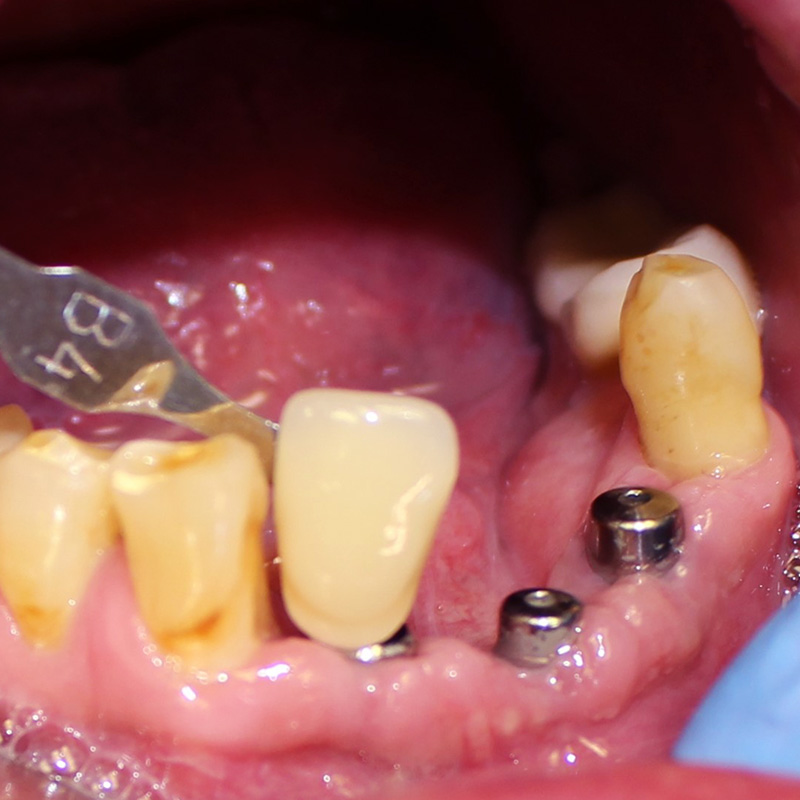

К нам в клинику обратился пациент с жалобой на частично отсутствующие зубы на нижней челюсти.

После осмотра и предварительной диагностики врач Мельников Алексей Владимирович рекомендовал провести имплантацию с последующим протезированием металлокерамическими конструкциями. После согласования плана лечения с пациентом приступили к лечению.

- установка 3 имплантов системы Alpha Bio;

- изготовление и установка металлокерамических коронок на имлантах системы Alpha Bio.